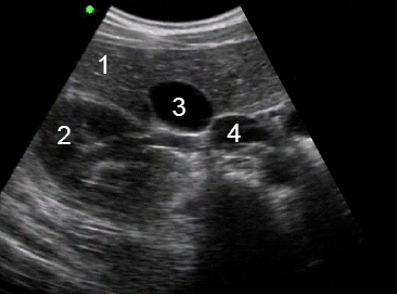

Gallbladder Anatomy Image

Liver

Right Kidney

Gallbladder

Inferior Vena Cava (IVC)